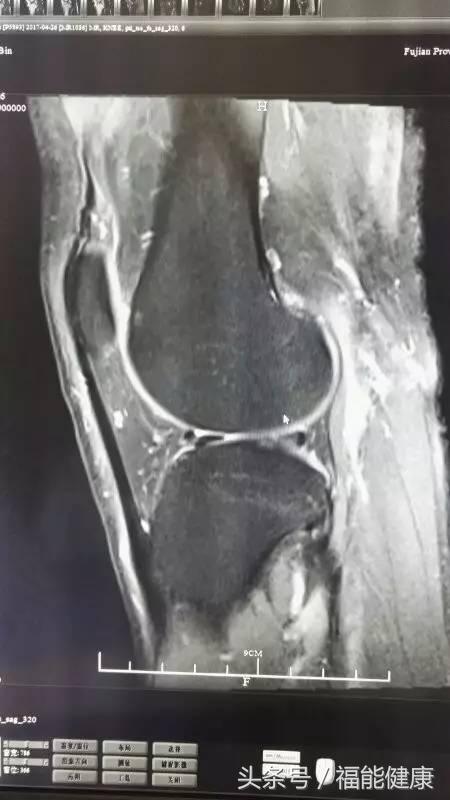

据福能健康管理中心放射影像科主任郑章和介绍,核磁共振对脑、甲状腺、肝、胆、脾、肾、胰、肾上腺、子宫、卵巢、前列腺等实质器官以及心脏和大血管以及骨关节都有很好的诊断功能。核磁共振的原理实际上是,将人体置于特殊的磁场中,用无线电射频脉冲激发人体内氢原子核,引起氢原子核共振,并吸收能量。在停止射频脉冲后,氢原子核按特定频率发出射电信号,并将吸收的能量释放出来,被体外的接受器收录,经电子计算机处理获得图像,这就是核磁共振成像的基本原理。

郑主任谈到,许多人对核磁共振检查的认识是有误区的。实际上,核磁共振是磁场成像,没有放射性,对人体无害,非常安全,这是核磁共振的优势之一。此外,核磁共振在发现病变及发现肿瘤方面也是一把好手,与其他辅助检查手段相比,核磁共振具有成像参数多、扫描速度快、组织分辨率高和图像更清晰等优点。

核磁共振检查不仅可以早期发现某些肿瘤、脑梗塞、脑出血、脑脓肿、脑囊虫症及先天性脑血管畸形,还能确定脑积水的种类及原因等。通过对头部及心脏等部位的核磁检查,在身体健康尚未发出红灯警讯前,早期发现心脏病、脑梗等高风险疾病隐患。当然,MR检查也不是万能的,在很多情况下也需要结合DR、超声、CT等手段,互为补充。同时,在诊断疾病的时候,尚需要密切结合临床其他资料。